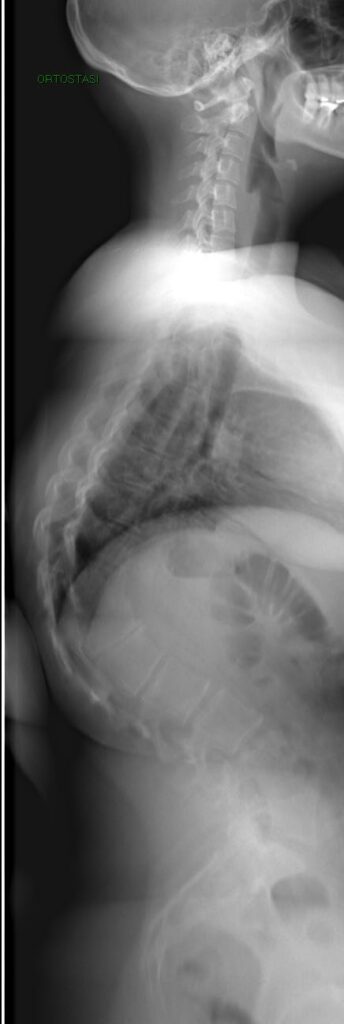

Quadro Clinico

- Il Dorso curvo

- Sede Toracica (apice tra T7 e T9) o Toracolombare (apice tra T10 e T12)

- IperLordosi lombare e cervicale di compenso

Cifosi dorsale rigida e dolorosa nell’adolescente

- Iperlordosi lombare non strutturata

- Antiversione della pelvi

- incurvamento delle spalle

Cifosi da Morbo di Scheuermann: Toracica

Cifosi da Morbo di Scheuermann: ToracoLombare